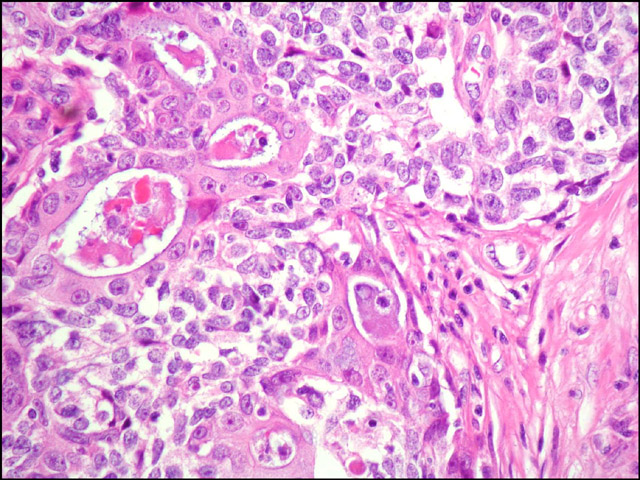

Descripción microscópica: el estudio histológico de ambas lesiones demuestra un carcinoma de células pequeñas que ulcera la epidermis, infiltra dermis e hipodermis e invade vasos linfáticos. La parte superficial de la neoplasia presenta un crecimiento difuso a expensas de células pequeñas y de tamaño intermedio (fig. 2). Además, se identifican focos de diferenciación escamosa (fig. 3) y áreas glandulares tapizadas por epitelio cúbico mucosecretor (fig. 4 y 5), adoptando una morfología que simula un carcinoma mucoepidermoide (fig. 6). También se advierten zonas con patrón angiomatoide, con formación de lagos hemáticos revestidos por células neoplásicos de mayor tamaño.

Carcinoma de células pequeñas.